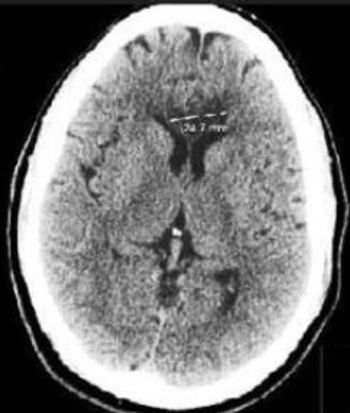

The patient's medical history was notable for hypertension, diabetes mellitus, and seizure disorder. Here, find images and lab results; then select a diagnosis.

Bilateral strokes of the corpus callosum are uncommon because of the rich blood supply of this structure from three main arterial systems.